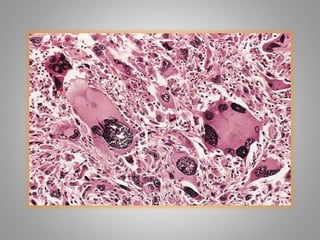

Dysplasia :

– Definiton: a loss in the uniformity of the individual

cells and a loss in their architectural orientation.

– Occurs mainly in the epithelia

– Dysplastic cells shows a degree of : pleomorphism,

hyperchromasia,increased mitosis and loss of

polarity.